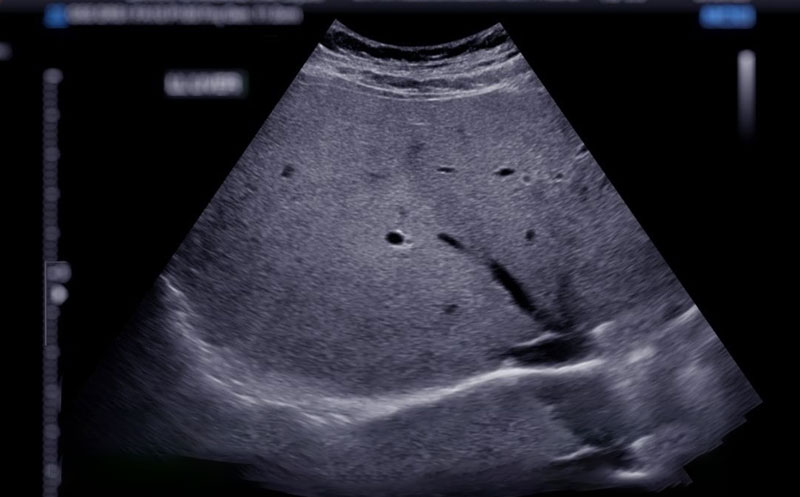

فیبرو اسکن کبد یک روش پیشرفته برای اندازهگیری سفتی بافت کبد است که میتواند به تشخیص میزان فیبروز (تشکیل الیاف کلاژن) کمک کند. برخلاف بیوپسی کبد که نیاز به نمونهبرداری با سوزن دارد، فیبرو اسکن یک روش کاملاً غیر تهاجمی و بدون درد است.

فیبرو اسکن کبد (FibroScan) یکی از روشهای غیرتهاجمی برای بررسی وضعیت کبد و تشخیص بیماریهایی مانند فیبروز، استئاتوز یا حتی سیروز است. بسیاری از افراد پس از انجام این آزمایش با یک گزارش عددی مواجه میشوند که درک مفاهیم آن برایشان دشوار است. در این مقاله، نحوه خواندن جواب فیبرو اسکن کبد و تفسیر جواب فیبرو اسکن کبد را بطور کامل برایتان شرح خواهیم داد تا بتوانید بهتر تصمیم گیری کنید که چه اقداماتی بر اساس نتایج فیبرو اسکن کبد باید انجام دهید.